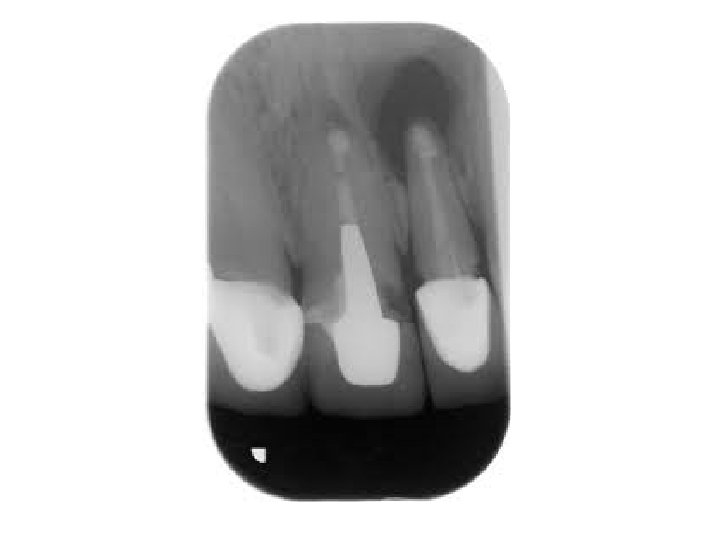

Granuloma periapicale • abgekapselte Ansammlung von Granulationsgewebe • Symptome: Keine Schmerzen, Devitalität des betroffenen Zahnes. • Röntgen: rundliche Form, scharfe Grenze, periapikale Aufhellung • Histologie: Cyst > 1 cm (Fluidum) Granuloma < 1 cm (Granulationsgewebe)